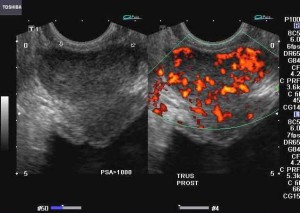

Alcuni trattamenti contro il carcinoma della prostata riducono le dimensioni del pene. Almeno questo e’ quanto emerso da uno studio che ha raccolto le denunce di molti pazienti curati con prostatectomia radicale, la rimozione chirurgica della prostata, o farmaci che agiscono sugli ormoni in combinazione con la radioterapia.carcinoma-prostata La ricerca e’ stata condotta da un team di ricercatori del Dana Farber/Brigham e dal Women’s Cancer Center. I risultati evidenziano che nessun uomo che ha seguito esclusivamente la radioterapia ha lamentato una correlata riduzione delle misure del pene. L’indagine e’ stata pubblicata sulla rivista ‘Urology’. I risultati della ricerca si basano sui dati raccolti attraverso il monitoraggio delle condizioni di 948 uomini trattati per cancro alla prostata che avevano subito una recidiva della malattia.

Venticinque uomini (il 2,63 per cento del gruppo) hanno lamentato la riduzione delle dimensioni del proprio pene dopo il trattamento: il 3,73 per cento a causa dell’intervento chirurgico e il 2,67 per cento a causa della radioterapia combinata con la terapia di deprivazione androgenica e lo zero per cento per la sola radioterapia. “Il cancro alla prostata e’ uno dei pochi tumori che permette ai pazienti di scegliere il tipo di trattamento – ha spiegato Paul Nguyen, coordinatore della ricerca – per questo e’ meglio che i pazienti siano informati con precisione sulle conseguenze delle differenti terapie in modo da poter scegliere tra la gamma di possibili effetti collaterali con maggior consapevolezza”.